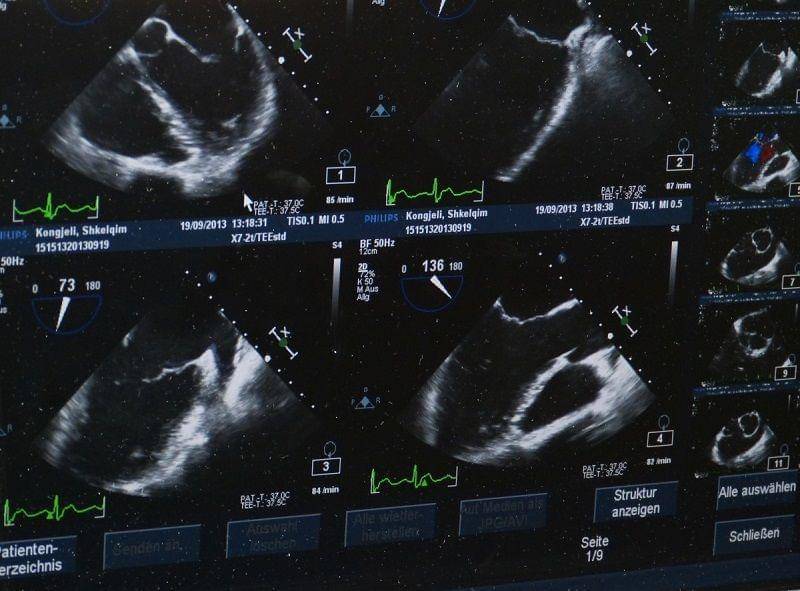

3. Pemeriksaan USG

Pemeriksaan USG (ultrasonografik) merupakan pemeriksaan yang wajib dilakukan pada ibu hamil trimester kedua.

Tujuan pemeriksaan ini sangatlah banyak. Salah satunya untuk mengecek kondisi janin dalam rahim.

Khususnya mengenai posisinya, ukuran tubuhnya, organ-organ apa saja yang sudah terbentuk, jenis kelamin, posisi plasenta, dan apakah volume air ketuban normal ataukah tidak. Selain itu juga dimaksudkan untuk melihat pergerakan janin.

Umumnya, gerakan janin mulai terlihat jelas saat usia kehamilan memasuki minggu ke-19.